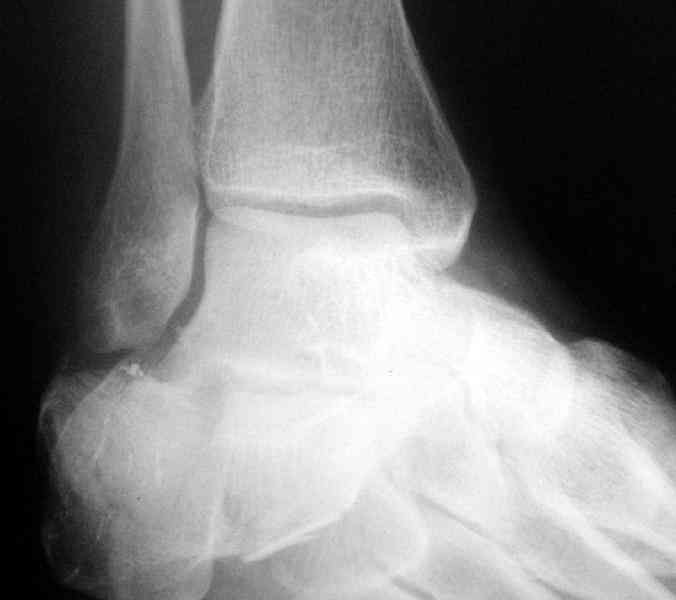

Re: Перелом пяточной кости

Пяточной пластиной

Открытый и закрытый способы лечения.